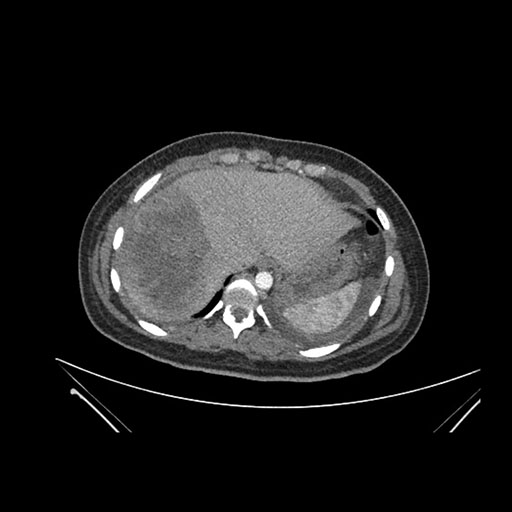

Imaging Analysis

Look through the patient's CT scan to identify any areas of concern for the necessary procedure.

Axial Venous

Based on initial findings, which issue(s) would you be most concerned about?